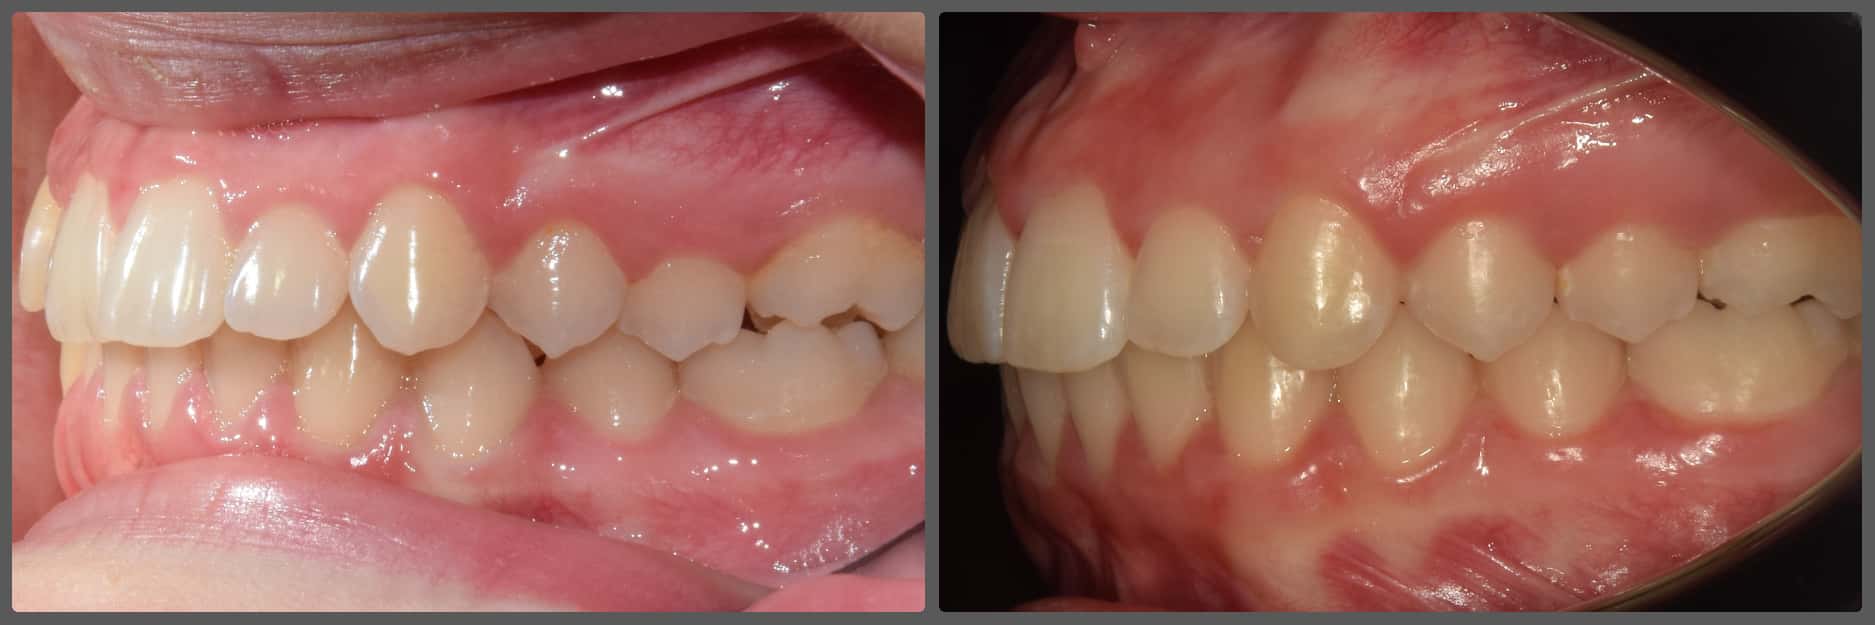

Balázs súlyos alsó torlódása miatt keresett fel magánrendelésemen. A diagnosztikus vizsgálatok során előbbin túl alsó-felső fogívszűkületet, valamint nyitott harapási hajlamot állapítottam meg. Kezelését Pitts21 alsó-felső rögzített fogszabályozó készülékkel kezdtük meg. A nyitott harapási hajlamot a hátsó fogakra helyezett harapásemelővel kontrolláltuk. A torlódott fogaknak tolórugóval és interproximális redukcióval teremtettünk helyet, és intermaxilláris gumihúzással tökéletesítettük a harapást. A fogszabályzó kezelés teljes időtartama alatt Balázs 110%-osan együttműködő volt, ezért 21 hónap alatt sikerült kiemelkedő végeredményt elérnünk.